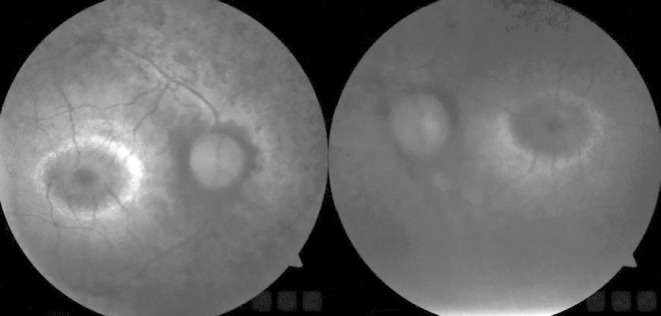

Jeune syndrome (JS), first described by Jeune as asphyxiating thoracic dystrophy, is an autosomal recessive osteochondrodysplasia with characteristic skeletal abnormalities and variable renal, hepatic, pancreatic, and ocular complications. Approximately 1 in every 100,000 to 130,000 babies is born with JS. Most patients with JS have respiratory distress due to inadequate lung development and many lose their lives due to respiratory failure. Those who survive have serious comorbidities. In terms of ophthalmological diseases, JS is classified among the hereditary syndromic retinopathies. Most, if not all, hereditary syndromic retinopathies can be analyzed in two main groups: inherited metabolic diseases and ciliopathies. The main cause of ocular pathologies in JS is genetic mutations in ciliary proteins that prevent normal function of retinal photoreceptor cells. Here we describe a patient with JS who presented with the complaint of night blindness. Although Snellen visual acuity was 20/20, the patient’s visual function was severely impaired due to photoreceptor dysfunction caused by ciliopathy secondary to the genetic mutation. This case shows that in patients with syndromic comorbidities accompanying nyctalopia, even those with perfect visual acuity, hereditary retinal dystrophies should be considered and asphyxiating thoracic dystrophy (JS) included in the differential diagnosis. Multimodal retinal imaging, including structural and functional assessments, should be used for the diagnosis and genetic counselling should also be provided.

Abstract Image